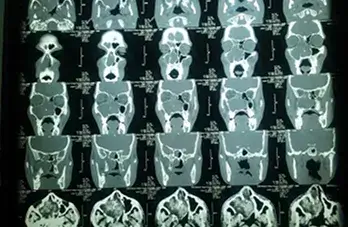

IMAGES

Barium Swallow

Bleeding Polypus Nose

Chicken Bone Nasopharynx

Conductive HL Audiogram

Endoscopic Ear Visualisation

Large Central Perforation

Mastoidectomy

Oropharyngeal Rhinosporidiosis

Tonsillitis

Fb Cricopharynx

Haller Cell

Inverted Papilloma Nose

Mastoidectomy 2

Mastoidectomy Cavity

Nasal Rhinosporidiosis

Neck Abscess

Palatal Ulcer

Retropharyngeal Abscess